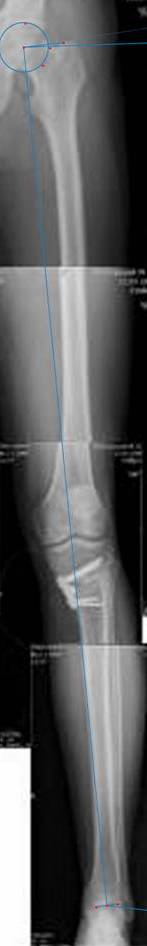

картинки оперированного пациента 40 лет, травма в 2006 году.

оперирован 06.11.2009г - корригирующая остеотомия большеберцовой кости.

Я картинку собрал с некоторыми погрешностями, если провести отвес от центра вращения головки бедра до середины голени (на пациенте),то имеется небольшой вальгус (гиперкоррекция)конечно она (гиперкоррекция) не достигает 10 гр, но 5 гр она достигает.

Проблема как сделать рентгеновские снимки а потом их совместить правильно, кто знает как решить этот вопрос. Ведь стандартные размеры рентгенкассет, оснащенные наши стационары отснять всю конечность с трех попыток!

Уважаемый д-р Батал Шушания,

К сожалению, не очень удачный пример. Если верить Р-граммам, имеет место быть дисплазия мыщелков бедренной кости с наклоном суставной линии. Это уже создает сложности получения хороших отдаленных результатов. Кроме того, по классике, необходима гиперкоррекция с созданием вальгуса 7-10 градусов для максимальной разгрузки медиального отдела КС. Если верить укладке, то линия сустава имеет четкий варусный наклон, поэтому результат операции м.б. кратковременным. В этих случаях показана двойная остеотомия бедра и тибии.

Впечатление искажает неправильная укладка.

Если сделать правильно, то видно, что бедренная кость в порядке, а цель остеотомии (низкой, кстати), не достигнута вовсе.

Сохраняется варус. Для того, чтобы создать вальгусную гиперкоррекцию, не моделируя при этом откровенный Х голени, можно сделать медиализирующую остеотомию.